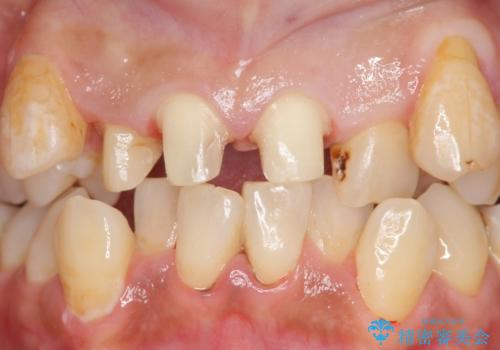

オールセラミッククラウン 長期間放置してきた前歯の虫歯治療

- 上顎前歯の見た目が気になるのでセラミックにしたいといらっしゃった方の症例です。

右上2は歯の神経が死んでおり、根尖病変を認めたため根管治療を行いました。

その後右上1,2番目及び左上1番目の歯に対してオールセラミッククラウンによる補綴を行いました。